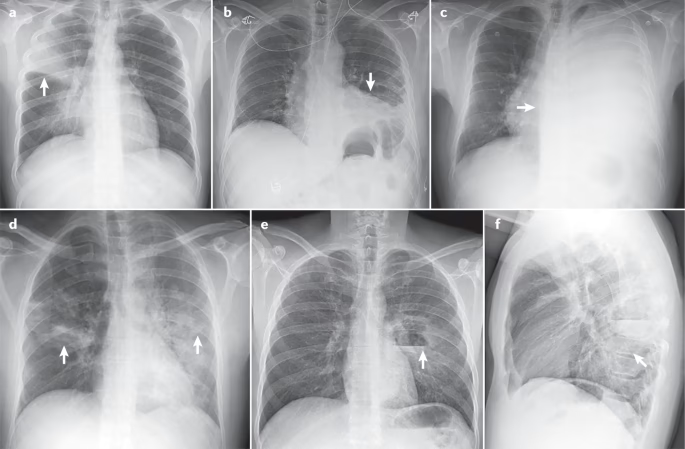

- Røntgenbillede af brystkassen: Dette er en afgørende undersøgelse, der kan visualisere infektionen. Lægen vil kigge efter hvide pletter (infiltrater) på billederne, og deres tilstedeværelse i begge lunger bekræfter diagnosen bilateral lungebetændelse.